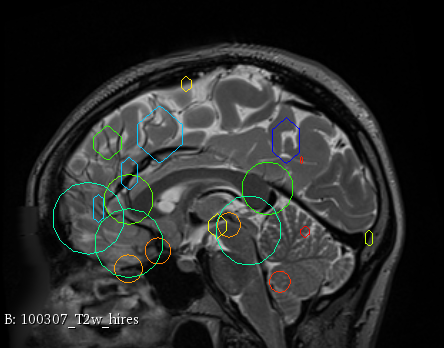

Figure 3 provides a scale-space visualization of feature matches for a single pair of MZ twins and NT siblings, where scale information is represented using the circle radius. Note that circles represent the intersection of 3D spheres with the visible slice and, thus, non-intersecting features are hidden in this 2D visualization.

It can be seen that different image modalities generally result in distinct, complementary feature correspondences throughout the brain, allowing a rich characterization of both anatomical and connectivity structure. In T1 and T2 images, features are mainly located in the frontal lobe, corpus callosum and brain stem. Smaller-scale features are also visible along various cortical regions, as well as in sub-cortical structures near the basal ganglia. Although highly correlated, T1 images show significantly more feature matches than T2 images. Moreover, images based on diffusion measures have less matches than in structural modalities. These matches are located mostly inside or near to white matter: larger-scale features in the corpus-callosum, and smaller-scale ones in the brain stem and along white matter bundles. While not shown in the figure, the set of matches found by combining two modalities (e.g., T1 + T2) generally corresponds to the union of those obtained with these individual modalities.

Comparing different sibling types, we observe a greater number of matches between MZ twins than NT siblings. This observation, which is easier to visualize in T2 and GFA images, is consistent with other analyses on twin datasets. In terms of feature location and scale, no obvious pattern can be seen when comparing these two sibling types. However, a more detailed analysis would be required to validate this assertion.